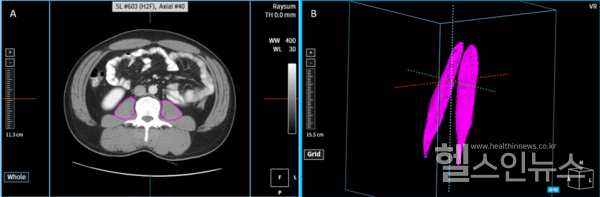

해당 연구에서는 520명 참가자의 CT 스캔 데이터를 활용해 요근 영역을 자동으로 분할하고 부피를 측정하는 nnU-Net 기반의 인공지능 모델을 개발한 것으로, 코어라인소프트의 AI 솔루션 AVIEW에서 구현됐다. 이 방법은 전문가가 요근 영역을 수동으로 직접 분할하는 것 보다 48배 더 빠르며, 인공지능이 자동으로 추정한 요근모양의 정확성을 의미하는 Dice score도 평균 0.927로 높은 효율성과 정확성이 입증됐다고 회사측은 설명했다.

서울아산병원 연구팀은 이번 연구가 다양한 CT 스캔 데이터를 활용한 의료인공지능모델의 가능성을 입증한 중요한 사례라고 언급했다. 특히, 대규모 대상자연구에서도 신뢰할 수 있는 결과를 제공해, 대량의 한국인 요근 부피 분석을 빠르게 수행함으로서 정상/비정상 범위 제 시 등과 같은 임상적으로 유용할 수 있음을 시사했다. 또한 이미 다른 검사목적으로 촬영된 기사 초안 2 수많은 CT데이터들을 재분석함으로서 근감소증의 추가적인 진단과 여러 연구가 가능하다고 전했다.